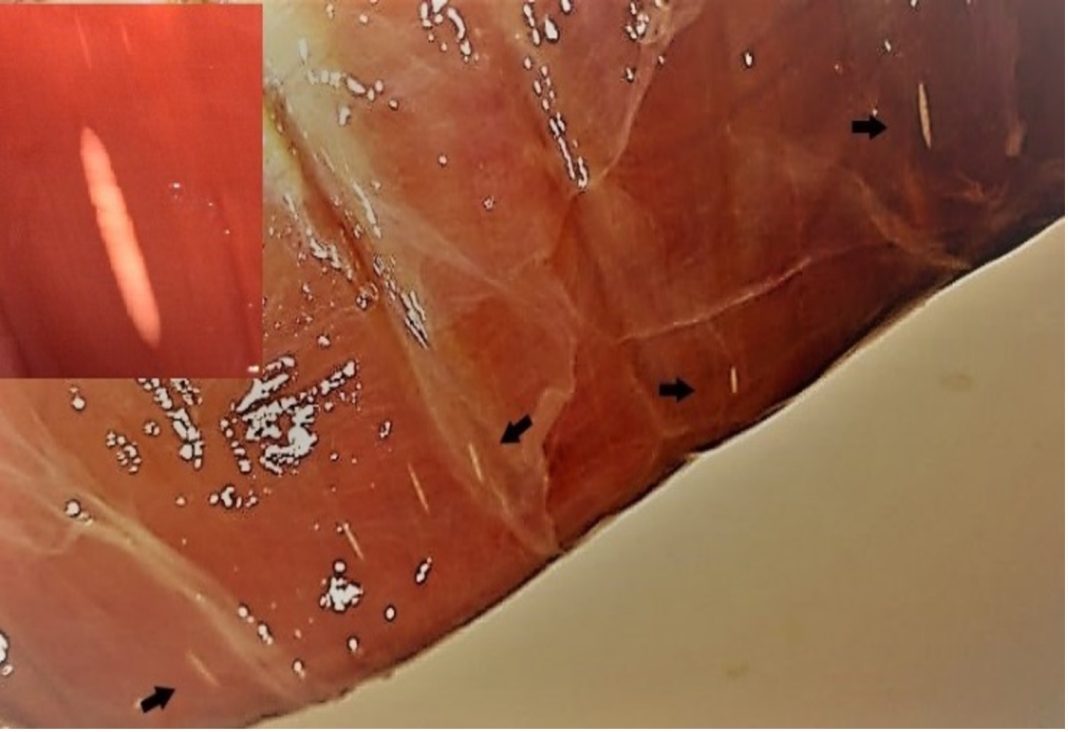

Lo anterior se trataría de quistes de mayor tamaño, visibles a simple vista, un hecho que ha generado la necesidad de contar con más información al respecto.

La Dra. Pamela Muñoz, Médico Veterinario, Magister en Ciencias Animales y Veterinarias con mención en Medicina Preventiva Animal, investigadora del Instituto de Patología Animal de la Facultad de Ciencias de la Universidad Austral de Chile, señala que “Sarcocystis sp. es un parásito intracelular que afecta a diversas especies de producción, generando pérdidas económicas asociadas a decomisos en plantas faenadoras.